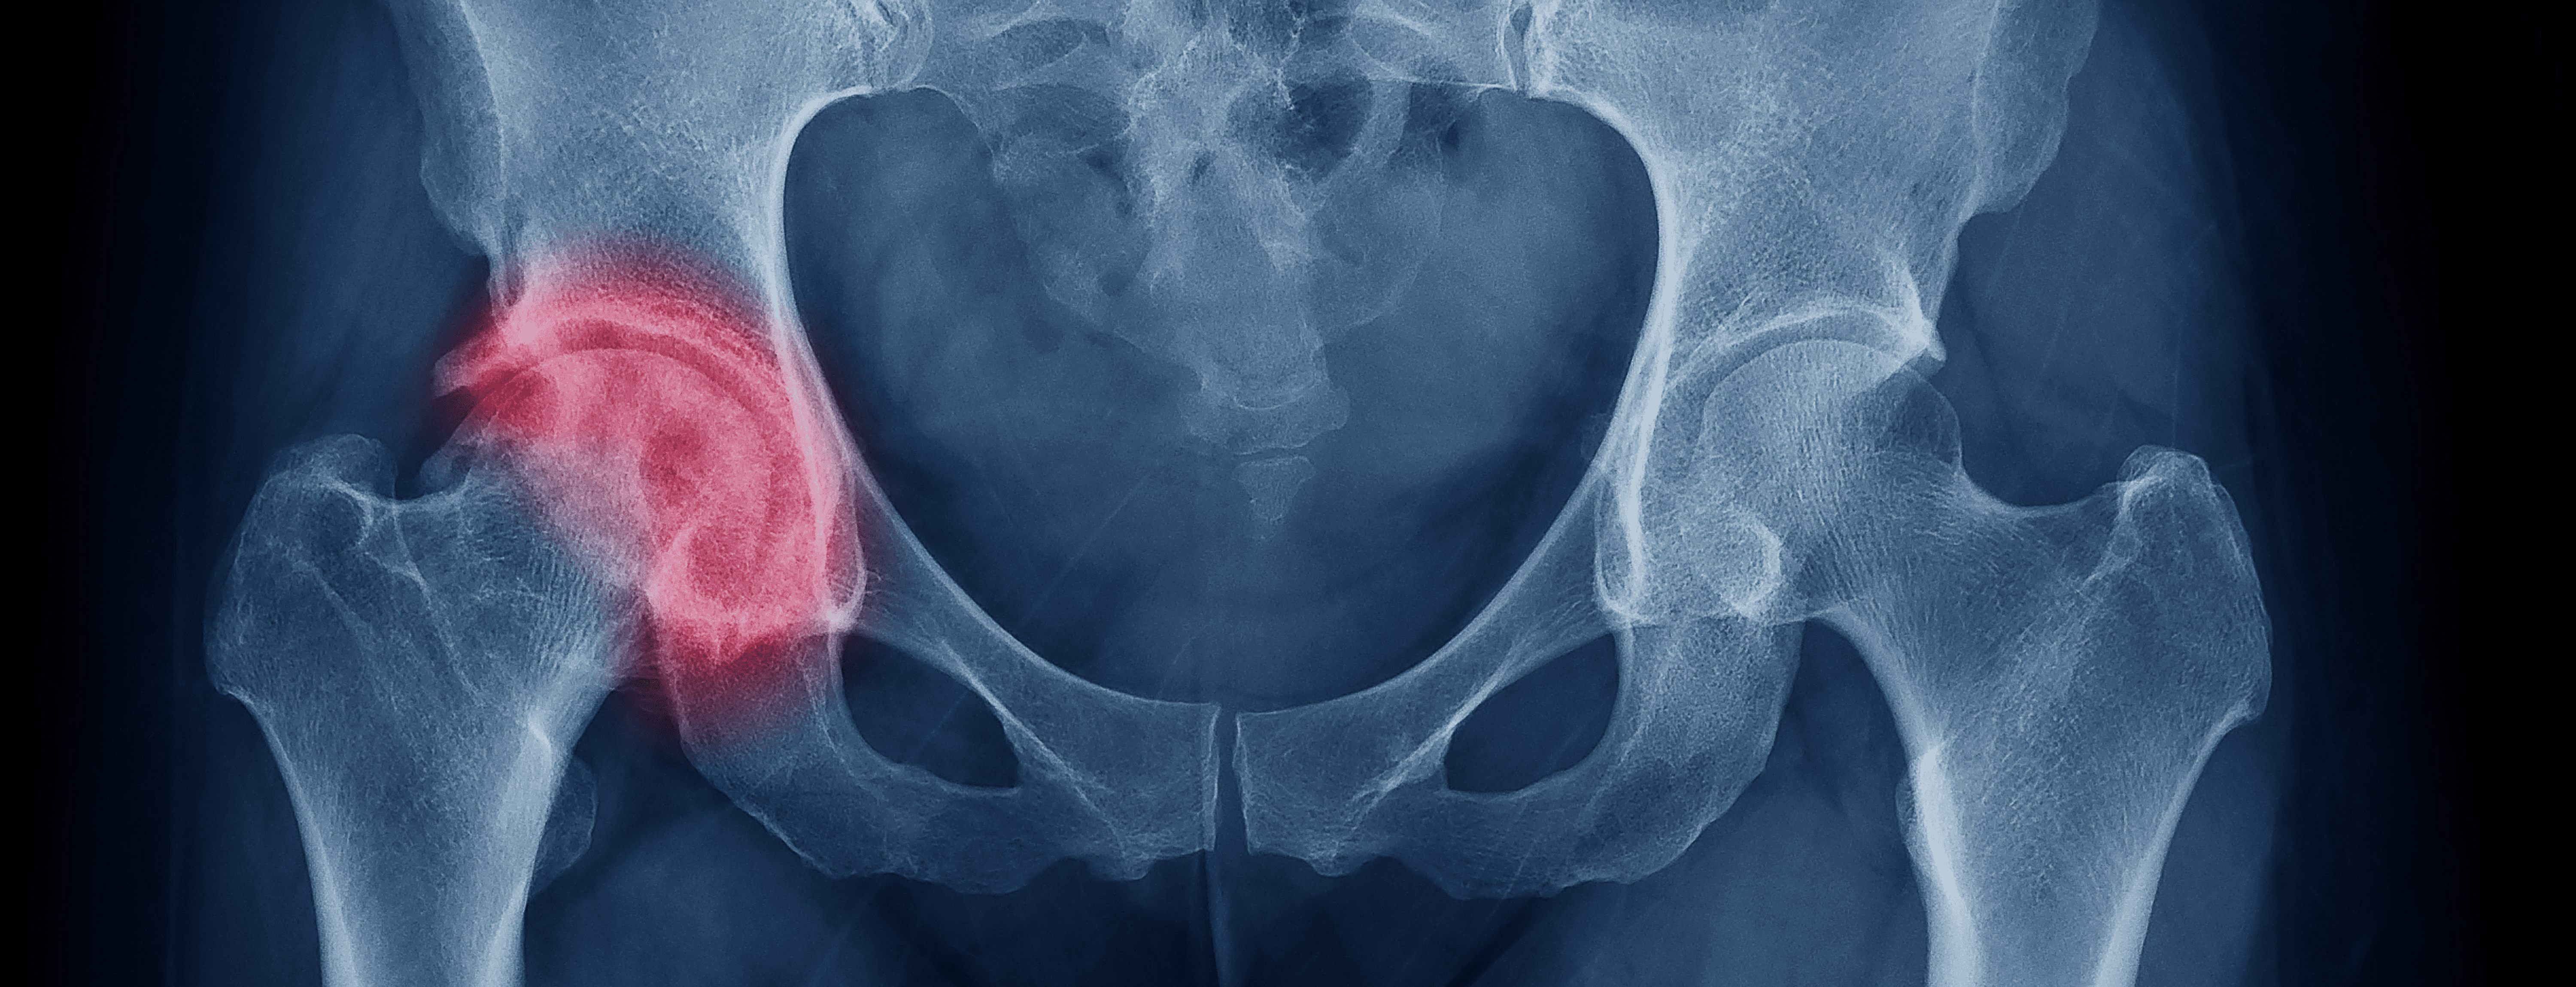

El dolor de cadera por lo general se presenta en la región inguinal, región glútea y en cara lateral de cadera. En ciertos casos puede presentarse como un dolor anterior de muslo e incluso de rodilla

Puede deberse a múltiples causas, dentro de las que destacan patología inflamatoria (sinovitis - bursitis) y degenerativa (artrosis)

La artrosis de cadera es una enfermedad degenerativa de la articulación, es decir que tiende a ir progresando el daño articular causando mayor limitación y dolor al paso del tiempo, siendo una patología irreversible

Si el dolor persiste de manera importante tiene indicación de cirugía, en la cual se reemplaza la articulación dañada por una prótesis total de cadera